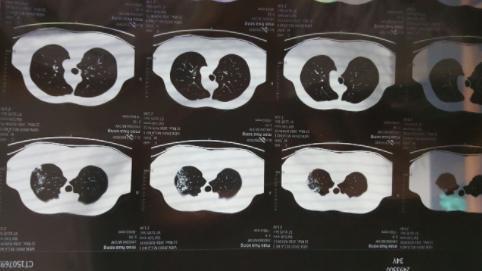

經(jīng)過了疫情的一波沖擊,大部分人都經(jīng)歷了一次新冠病毒的感染,陽康之后很多人都選擇拍胸部CT查看自己的身體情況,當(dāng)人們?cè)诳吹阶约旱臋z查單上寫著”肺部纖維灶“后嚇了一跳,大部分人詢問的問題都是”自己的肺部是不是纖維化了“、“肺部有玻璃陰影要緊嗎”?

對(duì)于人們最關(guān)注的這些問題,上海市胸科醫(yī)院呼吸與重癥醫(yī)學(xué)科副主任李峰表示,不必過度緊張,大部分人都只是出現(xiàn)了感染后的肺間質(zhì)異常,本身是沒有特別的其他癥狀,就像是一個(gè)傷痕,之后會(huì)慢慢恢復(fù)的,無需過多擔(dān)心,李峰表示,當(dāng)人在眼眶后檢查胸部CT,的確會(huì)發(fā)現(xiàn)肺部會(huì)有一些磨玻璃影,磨玻璃小結(jié)節(jié)等情況,這都是由于感染病毒之后才出現(xiàn)的,一般情況下不會(huì)再擴(kuò)大,而且過一段時(shí)間就會(huì)慢慢康復(fù)。

對(duì)于之前感染新冠病毒之后出現(xiàn)了肺部感染的人群建議等康復(fù)之后觀察隨訪,等到三個(gè)月到6個(gè)月左右,復(fù)查CT,如果沒有其他不適的癥狀,可以等到陽康之后3~6個(gè)月左右再檢查胸部CT,李峰解釋道,對(duì)于輕癥的肺炎患者,做檢查顯示肺部有纖維條縮影的情況無需特殊的干預(yù)。

專家表示,正常情況下,肺部出現(xiàn)纖維灶并不代表一定是壞的,這就像是人身體某個(gè)部位被劃傷之后留下的一個(gè)傷疤,不用特殊治療,也不用吃藥,肺纖維化分為兩種,一種是指特發(fā)性肺纖維化,第2種是繼發(fā)性纖維化,人們感染新冠后出現(xiàn)的屬于繼發(fā)性肺纖維化,重重就輕的,甚至充不上肺纖維化,所以無需過度擔(dān)心。